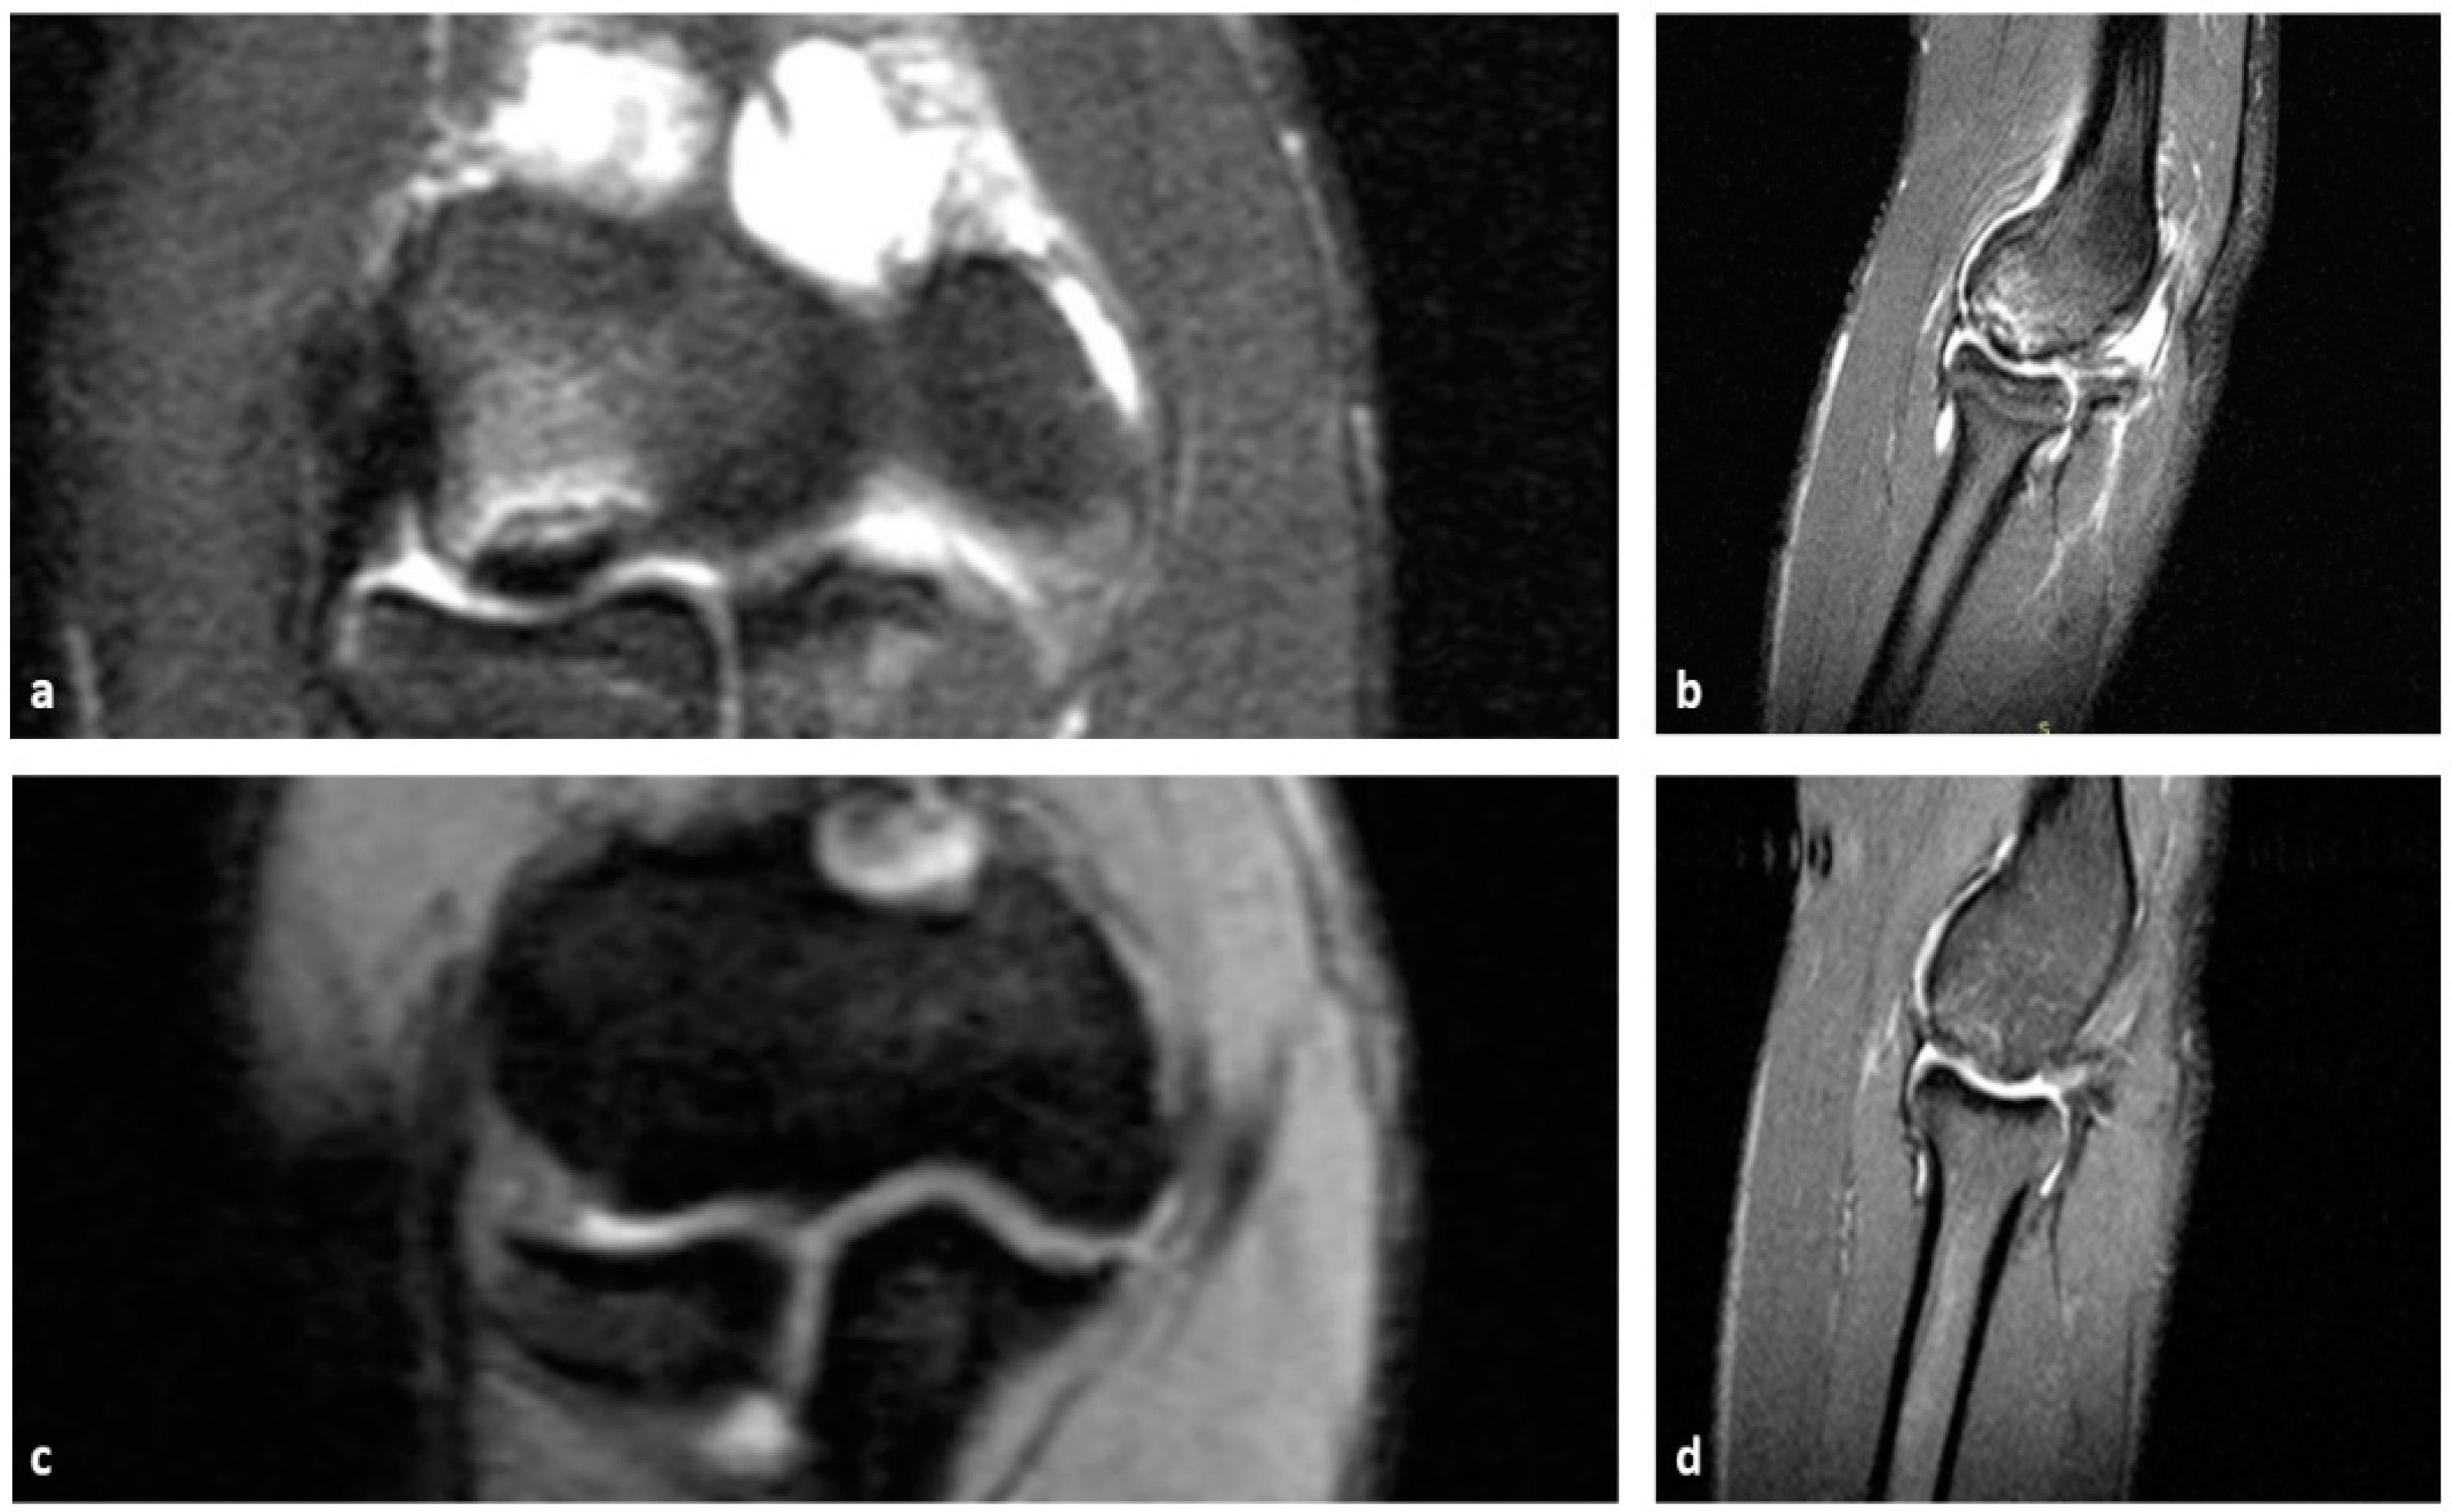

5. Imaging

- Kohyama, S.; Ogawa, T.; Mamizuka, N.; Hara, Y.; Yamazaki, M. A Magnetic Resonance Imaging–Based Staging System for Osteochondritis Dissecans of the Elbow: A Validation Study Against the International Cartilage Repair Society Classification. Orthop. J. Sports Med. 2018, 6, 232596711879462. [Google Scholar] [CrossRef]

- Iwasaki, N.; Kamishima, T.; Kato, H.; Funakoshi, T.; Minami, A. A Retrospective Evaluation of Magnetic Resonance Imaging Effectiveness on Capitellar Osteochondritis Dissecans Among Overhead Athletes. Am. J. Sports Med. 2012, 40, 624–630. [Google Scholar] [CrossRef] [PubMed]

- Nguyen, J.C.; Degnan, A.J.; Barrera, C.A.; Hee, T.P.; Ganley, T.J.; Kijowski, R. Osteochondritis Dissecans of the Elbow in Children: MRI Findings of Instability. AJR Am. J. Roentgenol. 2019, 213, 1145–1151. [Google Scholar] [CrossRef] [PubMed]